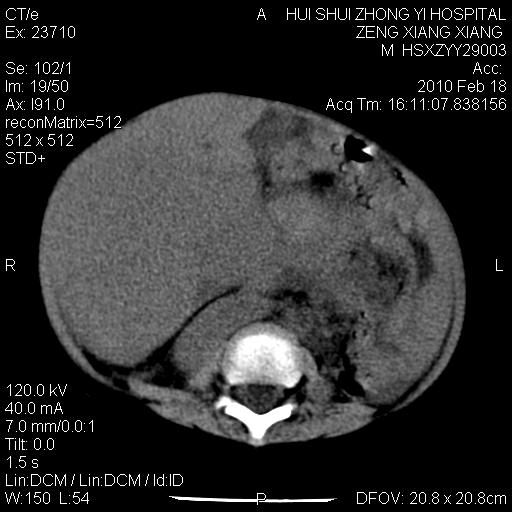

标题: PED3106:男,2岁,腹胀1月。 [打印本页]

标题: PED3106:男,2岁,腹胀1月。

定位腹膜后,肾上腺来源;

定性:恶性神经源性,肾上腺神经节母细胞瘤可能性大。

鉴别:肝母、肾母、肝脏中胚层错构瘤。

依据:年龄、有钙化,肾脏及肝脏受压移位。

肝母细胞瘤可能性大,右肾形态大体可见,不支持肾母细胞瘤,右肾移位不明显,肾上腺神经母细胞瘤可能性不大。